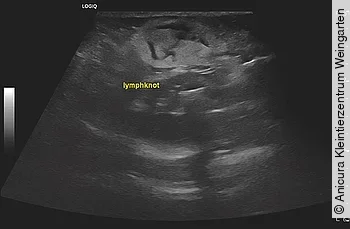

Abdominaler Ultraschall

Bei der Ultraschalluntersuchung des wachen Patienten in Rückenlage mit einem linearen 12 MHZ Schallkopf wurde eine generalisierte Vergrößerung des mesenterialen Lymphknotens festgestellt ([Abb. 2] und [3]). Die Darmschlingen zeigten eine gute Peristaltik mit einer fokalen Verdickung des Dünndarms und Zäkums. Kaudal der leicht gefüllten Harnblase wurde eine geringgradige Menge freie Flüssigkeit festgestellt. Beide Nieren wiesen eine gute Abgrenzung zwischen Kortex und Medulla auf. Die Milz zeigte eine mittelgradige Vergrößerung und das Parenchym war mit multiplen rundförmigen und hypoechogenen Herden versetzt, ca. 1x1 cm im Durchmesser. Die Leber stellte sich geringgradig vergrößert dar und zeigte abgerundete Leberlappenspitzen.

Auch im Ultraschall wurde im Inguinalbereich eine hypoechogene, rundförmige Struktur mit ca. 1,5 × 2 cm Durchmesser festgestellt und als Lymphknoten klassifiziert. Der Patient wurde daraufhin mit Alfaxan Multidose (Fa. Jurox) in einer Dosierung von 4 mg/kg i. v. sediert und es wurden Feinnadelaspirationen des Lymphknotens sowie von Milz, Leber und dem mesenterialen Lymphknoten durchgeführt.